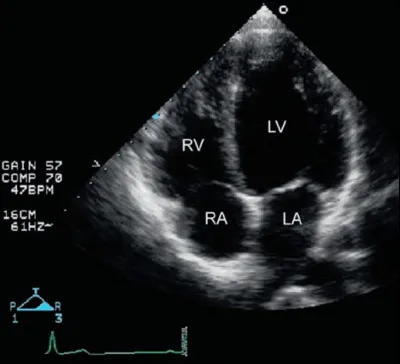

Un exemple de coupe d'échographie cardiaque. Saurez-vous me donner son nom ? (Faites-vous confiance, c'est faisable ;))